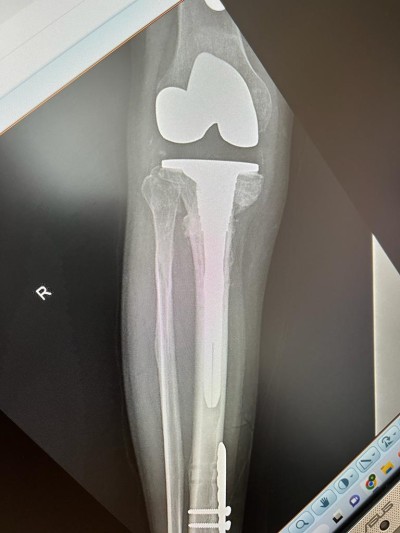

Interventie chirurgicala speciala de protezare a genunchiului cu pseudartroza de tibie proximala cu endoproteza necimentata de revizie

In cadrul sectiei de ORTOPEDIE – TRAUMATOLOGIE, s-a realizat cu succes o interventie chirurgicala cu grad ridicat de dificultate, la un pacient in varsta de 53 ani, care a suferit în urma cu aproximativ opt luni o fractura cominutiva bituberozitara de platou tibial cu intarziere în consolidare vicioasa.

In acest context, deformarea severa a tibiei si calitatea slaba a calusului osos impuneau o interventie chirurgicala de protezare a genunchiului cu endoproteza de revizie. Aceasta a fost efectuata de catre echipa medicala condusa de dr. CHIREA MARIUS, medic primar ORTOPEDIE-TRAUMATOLOGIE.

„Tinand cont de varsta tanara a pacientului, am optat la o versiune necimentata a endoprotezei și augmentarea la nivelul tibiei proximale (unde prezenta intarziere in consolidare si stoc osos precar) cu un con metalic Porocoat pentru a facilita si stimula osteoinductia. De asemenea, femurul si tija centromedulara tibiala care preia tensiunile din genunchi sunt necimentata. Acest dispozitiv protetic ne-a fost adus special pentru acest caz de firma Johnson and Johnson careia ii mulțumim. Totodata multumim si echipei operatorii și colegilor anesteziști”.

Rezultatul postoperator a fost un succes, s-a reusit alinierea genunchiului, dr. CHIREA MARIUS, medic primar ORTOPEDIE-TRAUMATOLOGIE obtinand o proteza necimentat primara stabila si cu mobilitate maxima.